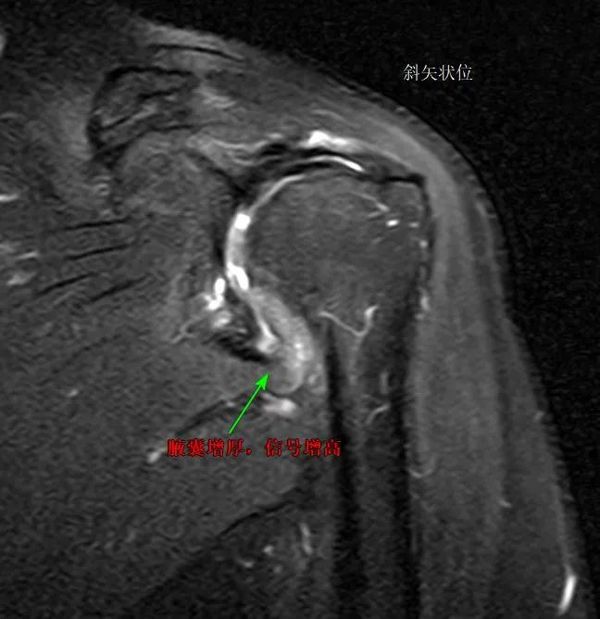

什么是肩袖损伤?肩袖损伤又叫肩袖创伤性肌腱炎,其原发性问题主要出现于肩峰撞击导致肩袖肌腱损伤,后又继发滑囊炎,可引起肩关节疼痛和活动障碍,严重影响患者生活质量。主要症状为肩关节疼痛及活动受限,还可以出现异常杂音、周围肌力减退等。